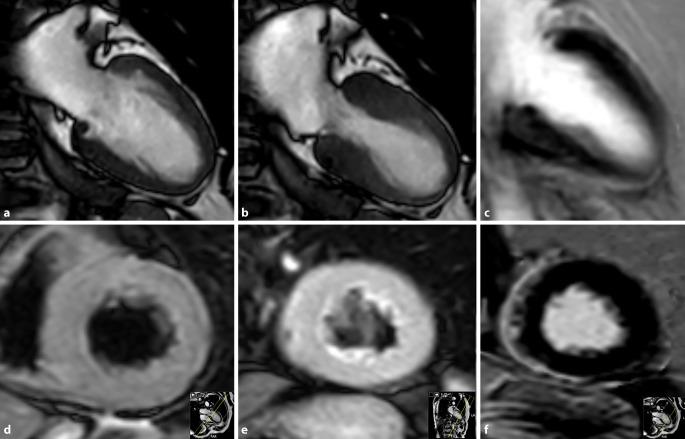

The strength of MRI is the ability to differentiate nonischemic cardiomyopathies from other diseases with similar morphofunctional aspects, based on the possibilities of tissue differentiation. In the case of dilated cardiomyopathy (DCM), for example, a differentiation from inflammatory DCM is possible. In the case of hypertrophic cardiomyopathy (HCM), obstructive and nonobstructive forms can be differentiated analogously to the echo but amyloidosis or Fabry disease can also be detected. Evaluation of the right ventricular function is reliable in arrhythmogenic right ventricular cardiomyopathy (ARVC). The use of MRI is also able to directly detect the characteristic fibrofatty degeneration. In the rare restrictive cardiomyopathies (RCM), MRI can track restriction and, for example by means of T1, T2 and T2* mapping, detect sphingolipid accumulation in the myocardium in the context of Fabry disease or iron overload in the context of hemochromatosis.

MRI的优势在于能够基于组织分化的可能性,将非缺血性心肌病与形态功能方面相似的其他疾病区分开来。例如,对于扩张型心肌病(DCM),可以与炎症性DCM进行区分。对于肥厚型心肌病(HCM),梗阻性和非梗阻性形式可类似于超声心动图进行区分,同时也能检测出淀粉样变性或法布里病。在致心律失常性右室心肌病(ARVC)中,对右室功能的评估是可靠的。MRI的应用还能够直接检测到特征性的纤维脂肪变性。在罕见的限制型心肌病(RCM)中,MRI可以追踪限制情况,例如通过T1、T2和T2* 成像,在法布里病的背景下检测心肌中的鞘脂蓄积,或在血色素沉着症的背景下检测铁过载。